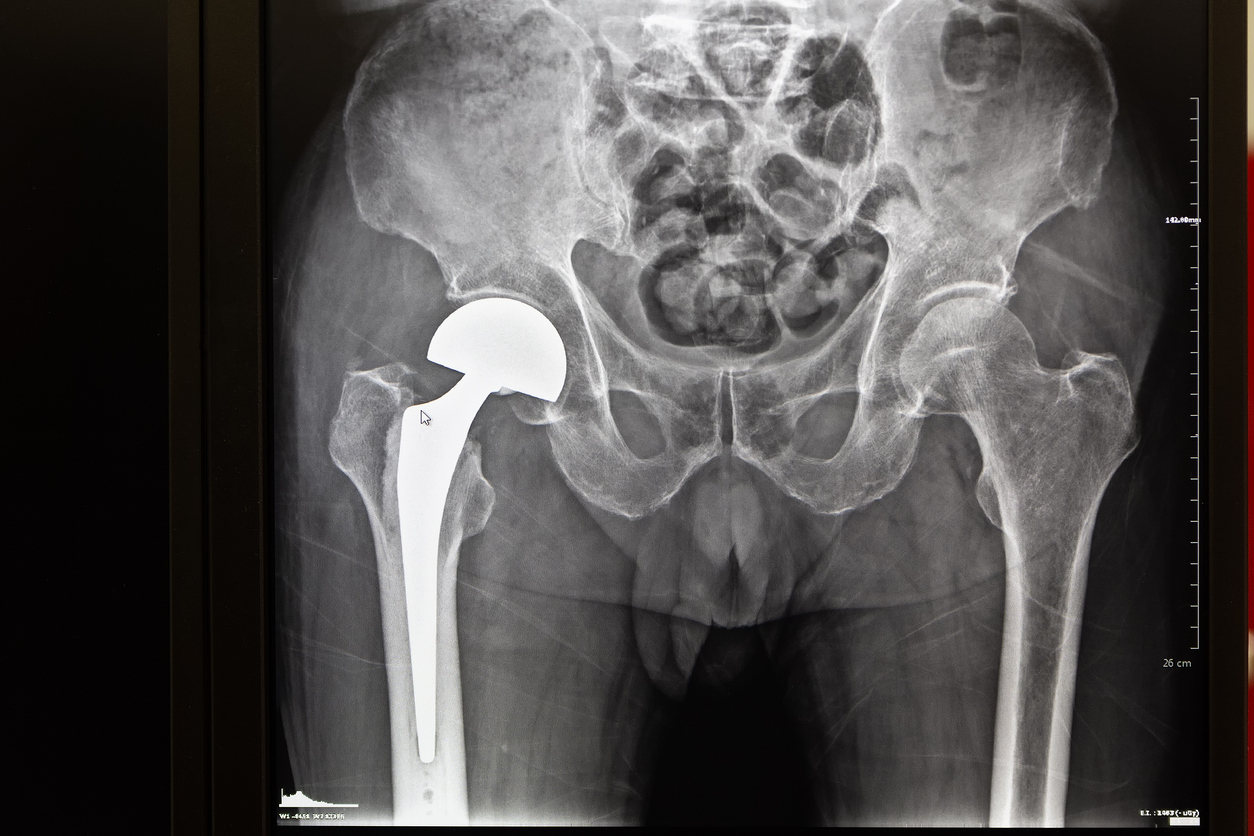

Changement de prothèse totale de hanche

La mise en place d’une prothèse de hanche est généralement réalisée suite à une usure arthrosique de cette articulation ou suite à une fracture. Malheureusement les contraintes mécaniques sur cette prothèse entraînent des phénomènes d’usure au bout de nombreuses années. Si la prothèse devient douloureuse, un descellement peut être suspecté qui conduira logiquement à un changement d’une ou plusieurs pièces de la prothèse.

C’est généralement une intervention plus lourde que la mise en place de votre prothèse initiale. Elle consiste en l’ablation de la prothèse usée ou infectée et à son remplacement par une autre prothèse pouvant se fixer correctement sur l’os abîmé. Ce remplacement peut se faire d’emblée ou secondairement s’il s’agit d’une infection.

Les différents types de descellement sont très variables et peuvent toucher le fémur et/ou le cotyle. C’est pourquoi les interventions de reprise sont toutes différentes, mais généralement la taille de la prothèse mise en place sera supérieure à votre ancienne prothèse.

Il arrive également qu’une seule partie de la prothèse soit changée en fonction de l’usure de celle-ci.